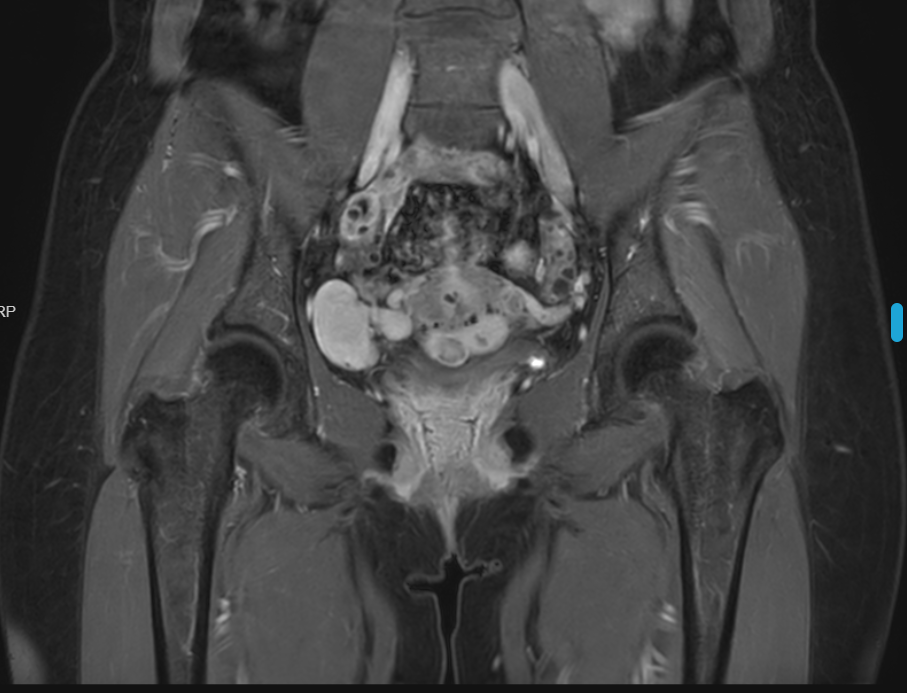

盆腔磁共振平扫+增强扫描:

影像所见:子宫表面欠光整,肌层、浆膜下见多发点状、结节状T1低信号,T2稍低信号,边界清楚,大者长径约14.5mm,不均匀强化。右侧盆腔见三枚T1低信号T2稍高混杂信号,增强明显较均匀强化,边缘光整,大者约23.3mm*38mm。

MRI提示:

1.子宫多发肌瘤;

2.右侧盆腔多发异常信号,考虑良性肿瘤可能,请结合临床。